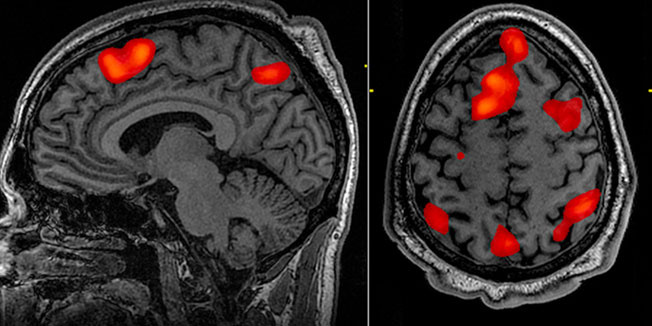

Znanstvenici su skenirali mozgove 152 14-godišnja adolescenta oba spola, i mjerili debljinu kore velikog mozga. Otkrivena je povezanost između vremena provedenog igrajući video igre i debljine kore u dvije regije mozga - lijevom dorzolateralnom prefrontalnom korteksu i lijevim frontalnim očnim područjima.

Prva regija zadužena je za don...